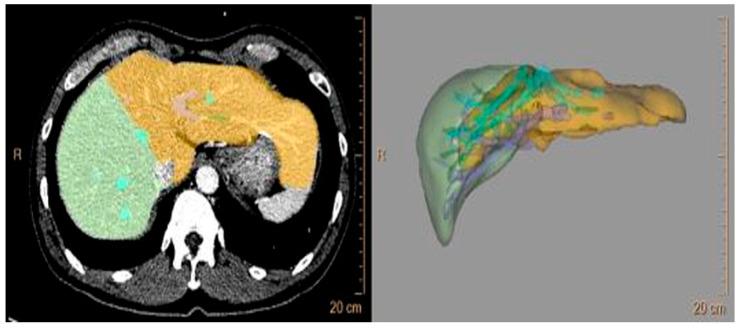

Sufficient liver regeneration after a right hepatectomy is important in living donors for preventing postoperative hepatic insufficiency; however, it differs for each living donor so we investigated the clinical factors affecting the rate of liver regeneration after hepatic resection. This retrospective case-control study investigated fifty-four living donors who underwent a right hepatectomy from July 2015 to March 2023. Patients were classified into 2 groups by the remnant/total volume ratio (RTVR): Group A (RTVR < 30%, n = 9) and Group B (RTVR ≥ 30%, n = 45). The peak postoperative level of total bilirubin was more elevated in Group A than in Group B (3.0 ± 1.1 mg/dL vs. 2.3 ± 0.8 mg/dL, = 0.046); however, no patients had hepatic insufficiency or major complications. The rates of residual liver volume (RLV) growth at Postoperative Week 1 (89.1 ± 26.2% vs. 53.5 ± 23.7%, < 0.001) were significantly greater in Group A, and its significant predictors were RTVR (β = -0.478, < 0.001, variance inflation factor (VIF) = 1.188) and intraoperative blood loss (β = 0.247, = 0.038, VIF = 1.182). In conclusion, as the RLV decreases, compensatory liver regeneration after hepatic resection becomes more prominent, resulting in comparable operative outcomes. Further studies are required to investigate the relationship between hematopoiesis and the rate of liver regeneration.

对于活体供肝者而言,右半肝切除术后充分的肝脏再生对于预防术后肝功能不全至关重要;然而,每个活体供肝者的情况有所不同,因此我们研究了影响肝切除术后肝脏再生率的临床因素。这项回顾性病例对照研究纳入了2015年7月至2023年3月期间接受右半肝切除术的54名活体供肝者。根据残余/总体积比(RTVR)将患者分为两组:A组(RTVR < 30%,n = 9)和B组(RTVR≥30%,n = 45)。A组术后总胆红素峰值高于B组(3.0±1.1mg/dL对2.3±0.8mg/dL,P = 0.046);然而,没有患者出现肝功能不全或严重并发症。A组术后第1周残余肝体积(RLV)增长率(89.1±26.2%对53.5±23.7%,P < 0.001)显著更高,其显著预测因素为RTVR(β = -0.478,P < 0.001,方差膨胀因子(VIF)= 1.188)和术中失血量(β = 0.247,P = 0.038,VIF = 1.182)。总之,随着RLV降低,肝切除术后代偿性肝脏再生更为显著,从而使手术结局相当。需要进一步研究来探讨造血与肝脏再生率之间的关系。